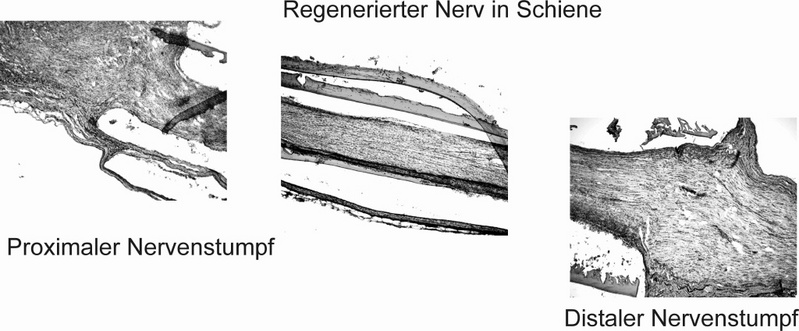

BERLIN (eis). Berliner Forscher haben eine Nervenschiene entwickelt, mit der durchtrennte periphere Nerven etwa nach einem Unfall sofort zusammengeführt werden können. Die verletzten Nerven wachsen darin problemlos wieder zusammen.

Sie besteht aus Chitosan, einem Abkömmling von Chitin aus Insektenpanzern. Das Material ist Protein-frei und induziert daher im Körper keine Abstoßungsreaktionen; es wird nach acht Wochen im Gewebe abgebaut. Die Schiene ähnelt einem Streifen Cellophan-Papier. Das Röllchen wird auseinandergezogen und zwischen die durchtrennten Nervenenden gespannt. Wird es gelockert, rollt sich das elastische Band um die Stümpfe und paßt sich dabei wie eine Spirale ohne Druck der Nervendicke an. Der Wickel verbindet die Nervenenden und wird mit Fibrinkleber fixiert.

Zwischen den durchtrennten Enden wächst dann der Nerv durch den Tunnel der künstliche Scheidewand zusammen.

"Belegt wurde dies bei Ratten, denen ein Zentimeter aus dem Ischiasnerv entfernt worden war", so die Forscherin. Die Innervation der Muskeln durch den Nerv sei acht Wochen nach der Therapie demonstriert worden. Auch habe sich neues Bindegewebe um den zusammengewachsenen Nerv gelagert. Eine Neurombildung - die bei durchtrennten Nerven oft vorkommt - sei nicht registriert worden.